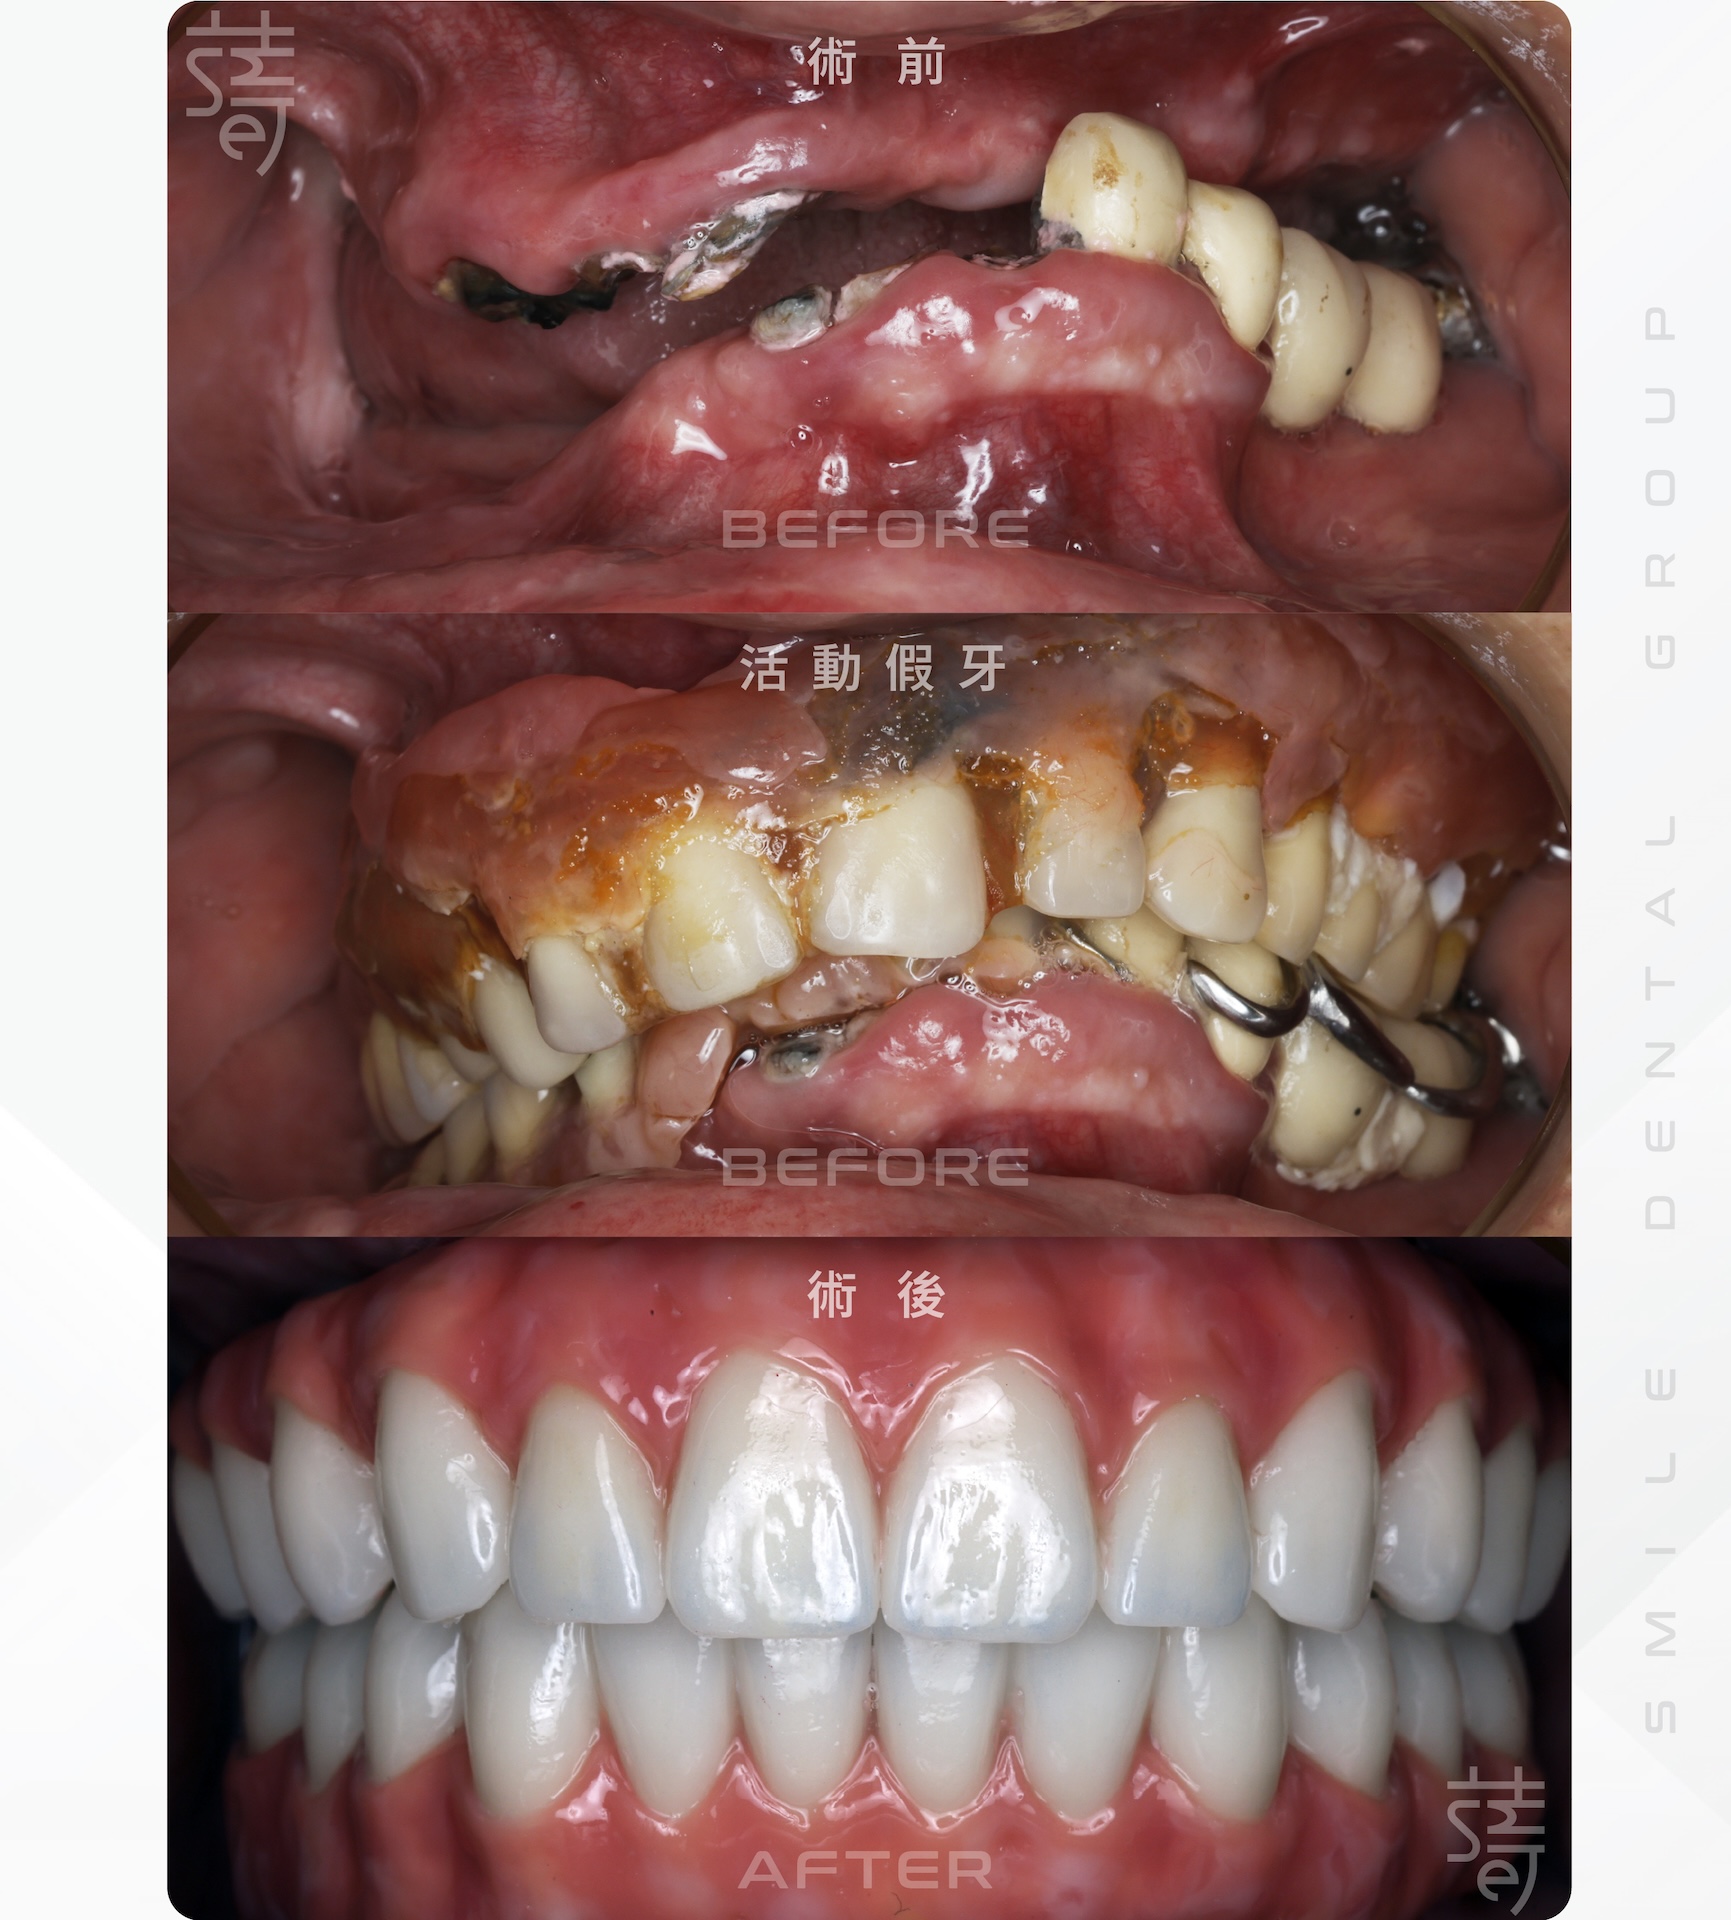

還不到 40 歲全口幾乎壞光,二十多年來只能依靠活動假牙勉強度日。假牙頂多撐一年多就得重鋪黏著劑,平時還要靠市售產品固定。最困擾的是,講課時假牙常晃動,語速一快便口水飛濺、發音漏風,授課品質大打折扣。直到僅存的牙根也開始鬆動,他才驚覺問題已到臨界點。

By his late thirties, he had lost nearly all of them, relying on dentures that never fit quite right. They slipped when he lectured, muddled his speech, and made him self-conscious in front of his students. Adhesives and constant adjustments offered only temporary relief, and eventually, even the few roots left began to fail.

若採傳統重建,療程需多年且多次補骨,恐影響教學。最終,團隊為他規劃諾保科 All-on-4,全程一天即可完成植體與假牙銜接,幾乎無縫回歸日常。

Traditional treatment would have meant years of bone grafts and delays. Instead, the team turned to Nobel Biocare’s All-on-4, restoring his teeth in a single day and allowing him to return to life without interruption.

賴醫師回憶:「第一次檢查時,莫教授就說想立刻裝上固定假牙。但我坦白告訴他:你的骨頭條件有限,尤其是上顎,骨質薄弱,甚至距離鼻竇不到 3 公釐,因此當天無法立即裝上固定假牙。不過,我們會先為你製作臨時活動假牙,既能維持自然外觀,也提供基本咀嚼功能。」

Dr. Lai recalled, “During our first consultation, Professor Mo told me he wanted to have permanent teeth fitted right away. I had to be honest with him: his bone structure, especially in the upper jaw, was too weak, and the distance to the sinus was less than three millimeters. That made it impossible to place permanent teeth on the day of surgery. Instead, we prepared a temporary set of removable teeth, which would preserve a natural appearance and allow basic chewing function.”

莫教授:「起初我有些失望,但很快就佩服醫師的誠懇與周全規劃,也因此安心把全口重建交給蒔美。」

Professor Mo: "At first, I was disappointed, but I quickly came to admire his candor and careful planning, and I felt confident entrusting my full-mouth reconstruction to them."

完成 All-on-4 後,他的牙齒自然穩定,就像「長出第三副牙」。親友都說他神采奕奕,更顯年輕,也更能自在教學、出國與開會,重拾自信與行動力。

Now, months after the All-on-4 procedure, my teeth feel completely natural and stable—like having a third set of teeth. Friends say I look younger, and I can teach, travel, and meet with ease, regaining both confidence and mobility.